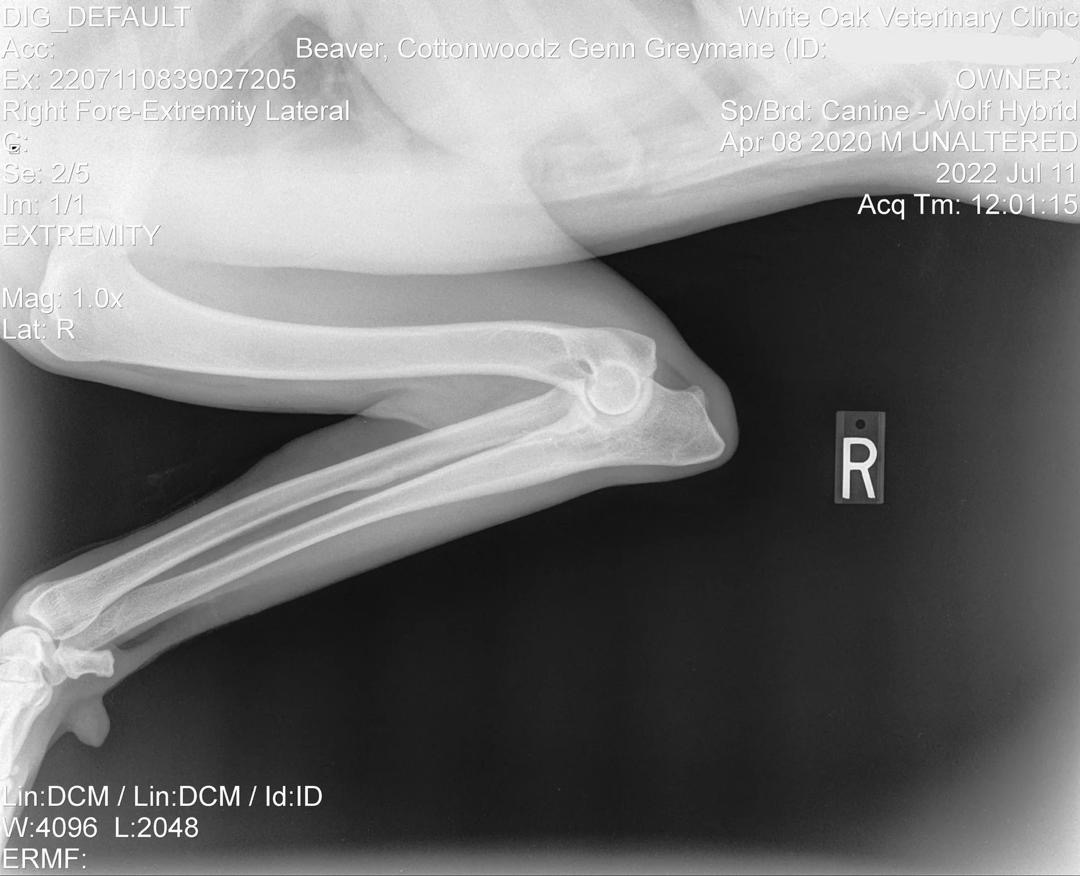

Genn Official Right Elbow X-Ray

Official Right Elbow X-Ray

OFA Elbow Evaluation: Normal